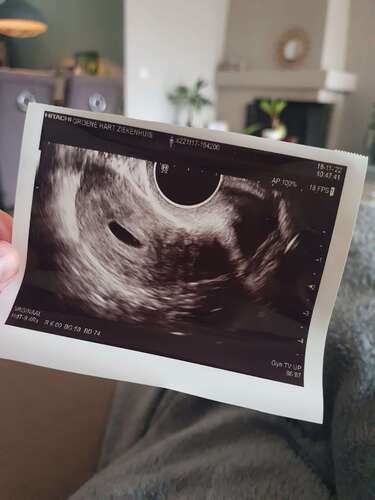

Ik weet dat dit een vroege echo was, maar ik sukkel al van mijn 14 jaar met baarmoederproblemen. Daarom dat we even gingen kijken of het zeker wel in men baarmoeder zat en niet er buiten. En of alles wel inorde was met de baarmoeder zelf.

Ik hoop met goede hoop mee voor je! Volgens mij zie je met 5 weken ook niet meer dan wat je hebt gezien, dus nog geen enkele reden om aan te nemen dat her niet goed zit. Zekerheid heb je nooit, maar t klinkt goed!

(2 weken krijg je cadeau omdat ze rekenen vanaf de 1e dag van je laatste menstruatie) feitelijk ben je 3 weken zwanger en dan is er simpelweg nog niet meer ontwikkeld. Precies zoals je gynaecoloog al hoopte.

Volgens mij is dat een normale echo bij 5 weken, hoe spannend ook en 3 weken is idd lang